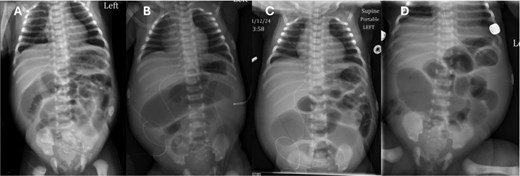

She underwent a diagnostic laparoscopy which revealed absence of abdominal wall bands. The procedure was converted to an exploratory laparotomy with incision in the right lower abdomen. The bowel was examined extracorporeally and focal narrowing with dilated bowel proximal was noted in the ileum (Fig. 3). There was mild venous congestion noted in the proximal bowel but otherwise appeared viable. This region was resected with ~10 cm of bowel proximal to the narrowing in order encompass areas of possible pneumatosis. A single layer primary anastomosis was created, followed by fascial and skin closure.

(A) Operative findings of ileal stenosis. (B) Postoperative resection with anastomosis. (C) Clinical follow-up with well healed right lower quadrant scar.